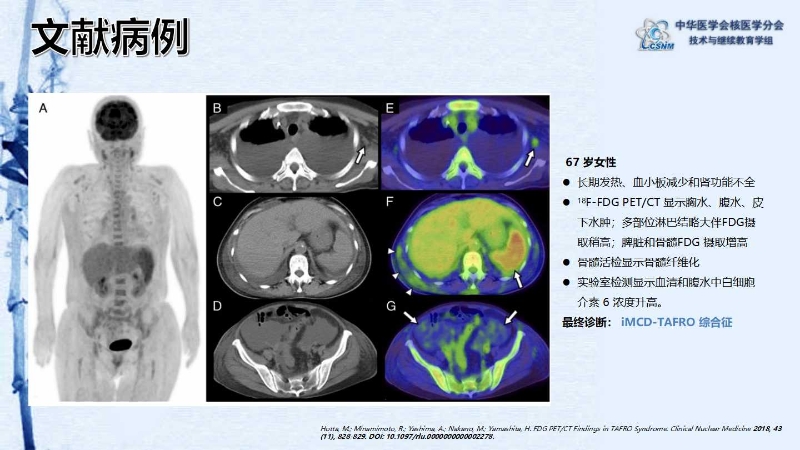

【CSNM继教学组】病例E54-赵红光:以TAFRO综合征起病的Castleman 病